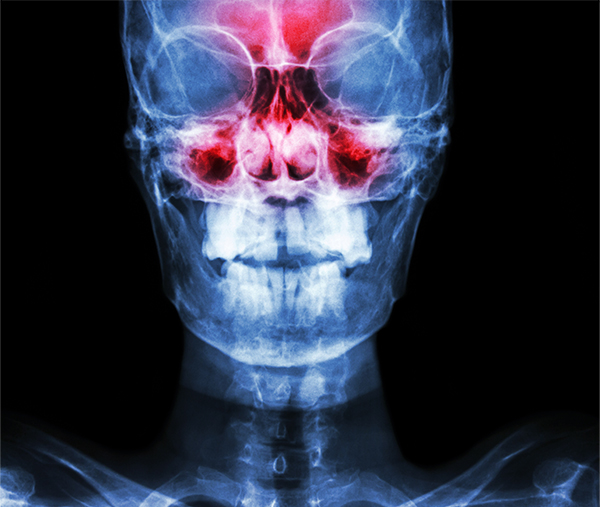

부비동염이란?

부비동염이란 코 주변의 부비동이 염증을 일으켜 불편함을 발생시키는 상태를 가리킵니다. 부비동은 얼굴뼈 내부에 있는 공기로 채워진 공간으로, 콧물과 점액을 생산하며 호흡을 돕는 중요한 역할을 담당합니다. 부비동염은 주로 바이러스나 세균에 의해서 감염이 되고, 다음과 같은 증상을 일으킵니다